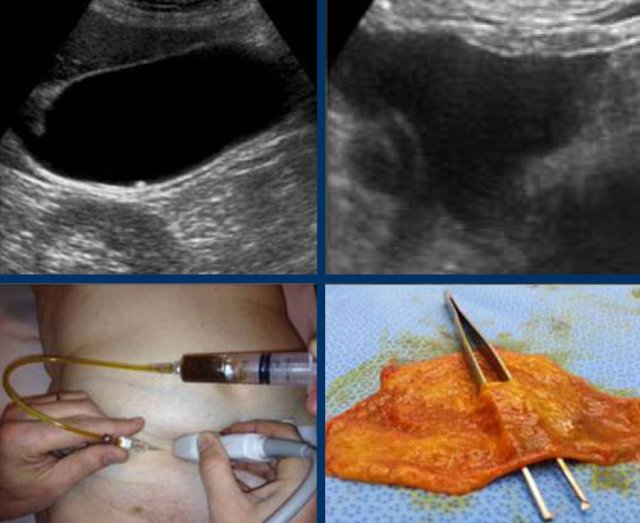

The images show a longstanding acute cholecystitis.

Note the large area of inflamed and indurated fat (asterisks) and the relatively small, somewhat compressible gallbladder.

This reflects a lumen filled with pus where the diseased mucosa is not capable of producing mucus under pressure anymore.

Drainage revealed pus.